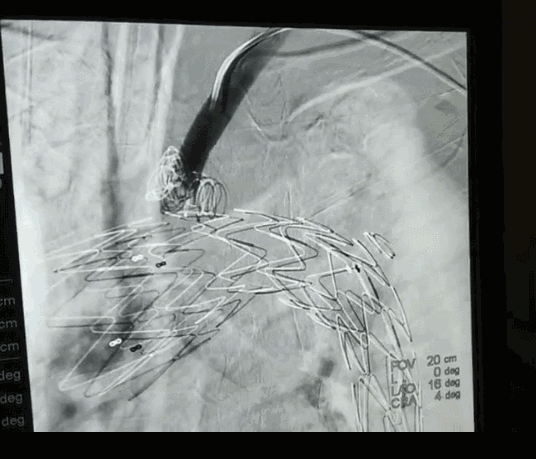

由于患者主动脉弓支架锚定区直径近36mm,需要大型号的支架,整个南阳市内没有,经联系只有郑州有,大雪封路,没有班车及快递,马上启动应急预案,连夜从郑州坐火车把支架运回,在住院第二天上午急诊手术,行腋腋动脉转流+主动脉覆膜支架植入+左锁骨下动脉弹簧圈封堵术,术后患者恢复顺利。

立即行CTA,明确诊断为Stanford B 型主动脉夹层,破口位于左锁骨下动脉根部,并且主动脉弓部明显增宽,左侧胸腔大量积液。此种情况非常危险,为主动脉夹层濒临破裂的征象,随时有发生破裂死亡的可能。